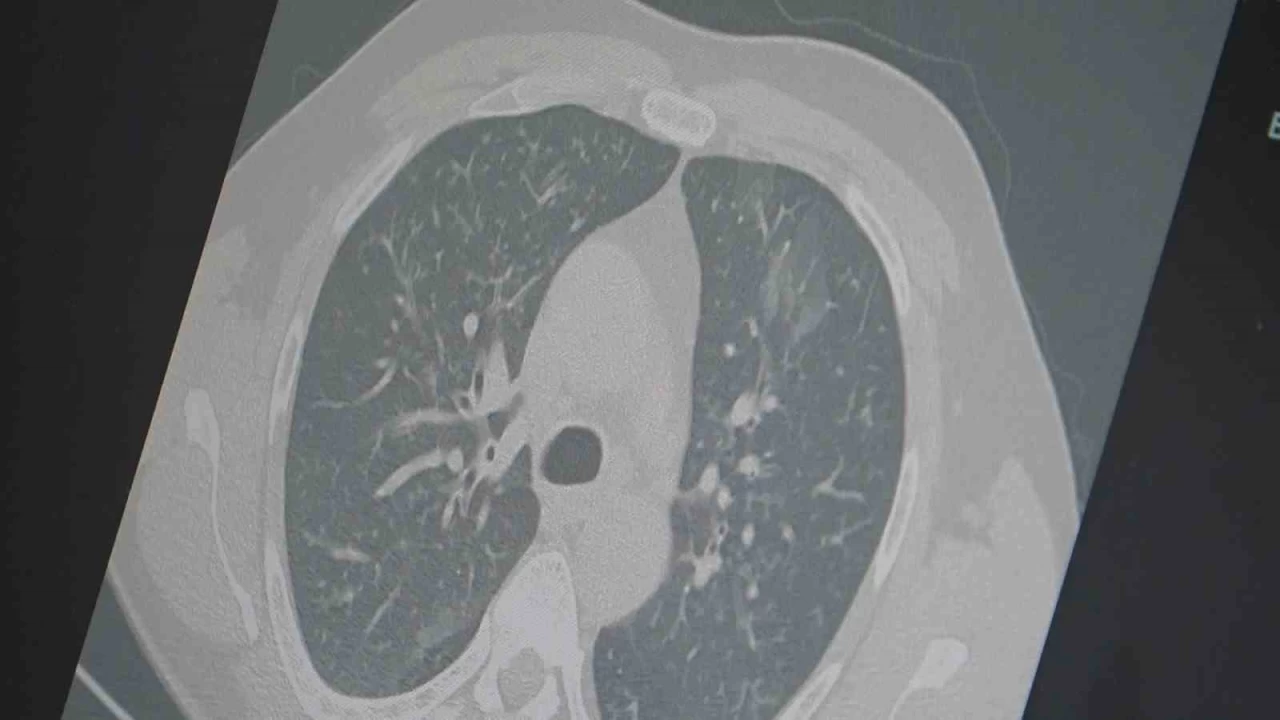

Dr. Özkaya, grip ve kovid 19'un zatürreye dönüşme riski taşıdığını vurgulayarak, "Grip veya kovid sonrası birçok hastamızda hastalık akciğerlere iniyor ve zatürre olarak karşımıza çıkıyor. Hastaneye yatan hasta sayısında da artış gözlemliyoruz" şeklinde konuştu.

"En ufak grip benzeri şikayeti olan vatandaşlarımızın evlerinde dinlenmelerini öneriyoruz. Uzamış öksürük ve nefes darlığı yaşayanların ise mutlaka doktora başvurarak akciğer röntgeni çektirmeleri ve uygun tedaviyi almaları gerekiyor."İHA